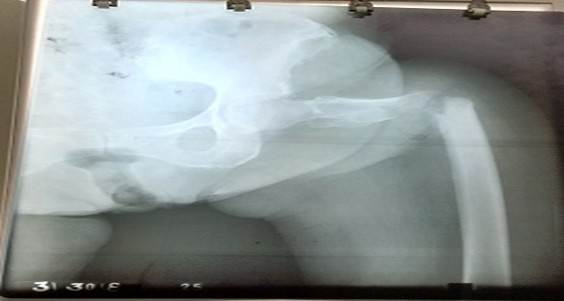

El segundo estadio es de vital importancia, para evitar la FP, que de ocurrir se produce la salida de células tumorales al hematoma fracturario y de allí al organismo. Las FP tienen cuatro características: son causadas por trauma mínimo o de forma espontánea, presencia de dolor o síntomas previos en la zona, trazo radiológico transversal y presencia de enfermedad previa local o sistémica (Figura 2). 25,26,27

Capanna R y Campanacci DA, 32 estiman el riesgo de FP cuando existe afección de más de un 50 % del diámetro cortical en los planos coronal y longitudinal (Figura 3).